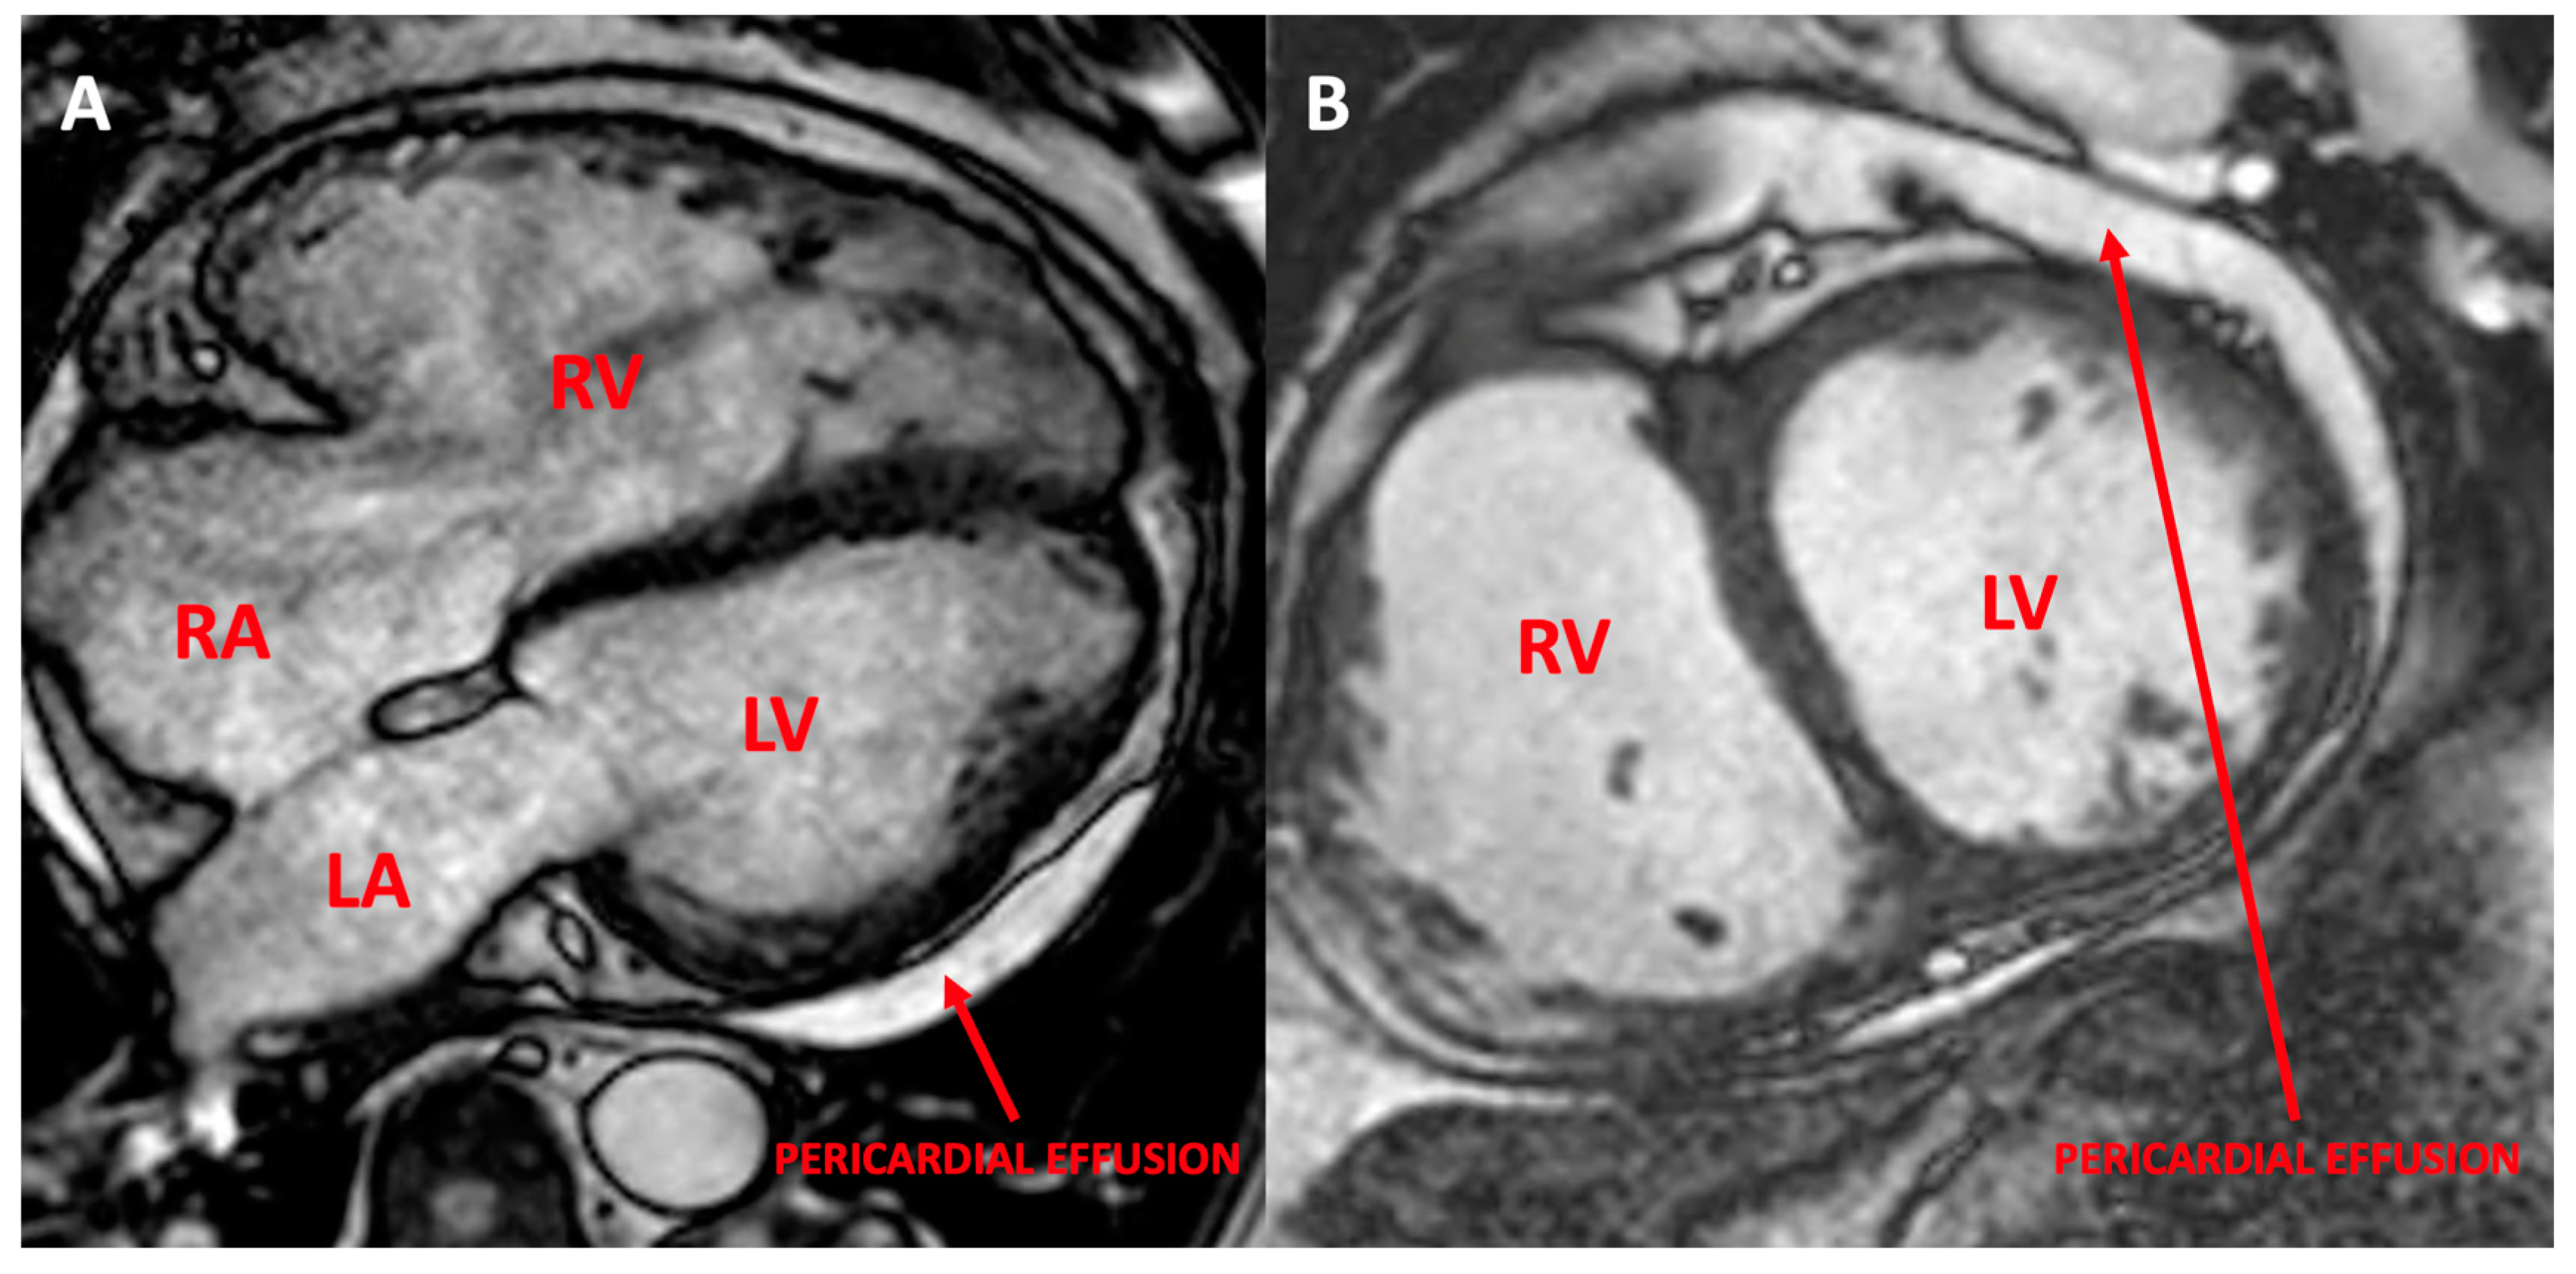

3.1.4. Patient 4